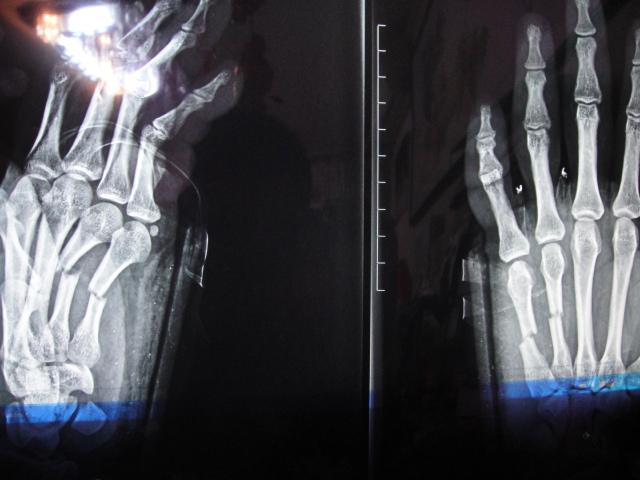

正直5.4青年节邮件大学篮球场上我因打球造成掌骨4 5骨折,长时间未批改作业请大家见谅。

据初步估计会在2-3个月后痊愈,随后将组织大量香山活动,请大家踊跃报名。

以下有图片为证:

看不懂,觉得挺恐怖的。

断了,你拍的铁球啊...